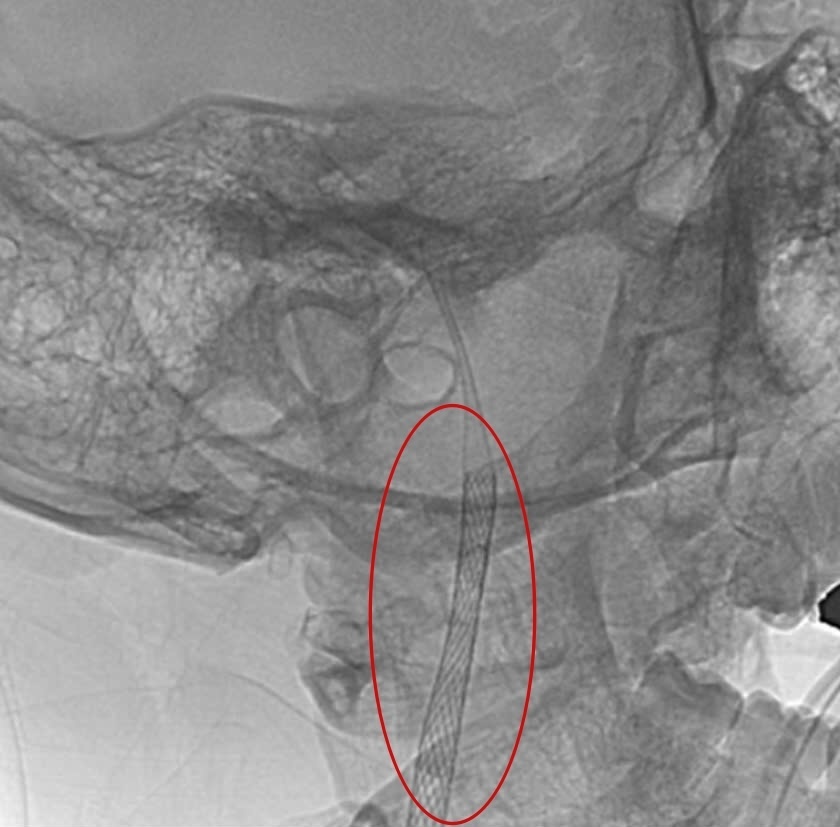

Các bác sĩ phải dùng hai stent chồng nhau để “gia cố” tổn thương dài đến 80 mm.

Trước khi tiến hành thủ thuật, anh A.M được bác sĩ trao đổi kỹ về tình trạng bệnh và phương pháp điều trị. Do vết bóc tách động mạch dài đến 80 mm, nên phải sử dụng hai stent phủ lên nhau để đảm bảo thông thoáng mạch máu.

Thủ thuật do bác sĩ Đức và ê kíp thực hiện diễn ra suôn sẻ trong vòng 3 giờ tại phòng Cathlab, dưới sự hỗ trợ của hệ thống trang thiết bị hiện đại, đặc biệt là hệ thống chụp mạch số hóa xóa nền (DSA) tích hợp đa nhiệm - có thể chụp mạch máu tim, mạch máu não và mạch máu toàn thân. Từ vết rạch ở đùi, bác sĩ đưa ống thông có gắn stent luồn vào động mạch lên đến vị trí động mạch bị rách. Stent được đặt vào vị trí vết rách để “hàn” lại vùng động mạch cảnh, nhờ đó máu có thể lưu thông bình thường trở lại.

| Hình ảnh mạch máu của bệnh nhân sau khi được đặt stent. |